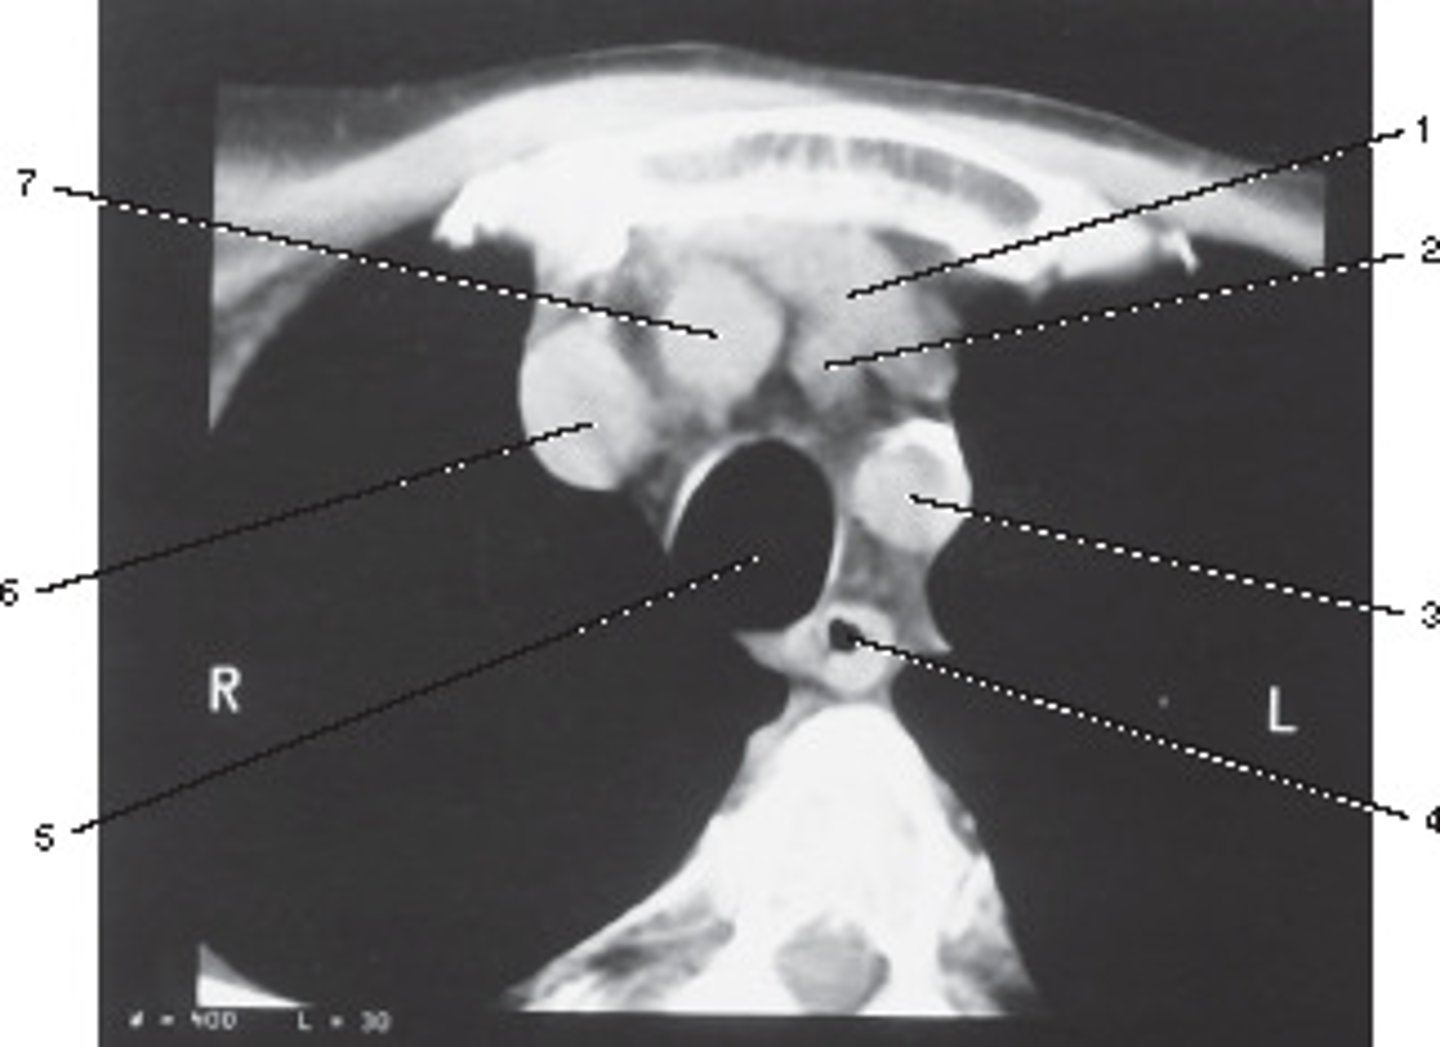

Number 2 corresponds to which of the following?

<p>Number 2 corresponds to which of the following?</p>

Dental Fillings; Metallic items cause star artifact

These streaking artifacts were most likely caused by:

<p>These streaking artifacts were most likely caused by:</p>

Number 3 corresponds to which of the following?

<p>Number 3 corresponds to which of the following?</p>

Enlarged Thyroid

What pathological process best describes the abnormal finding in this image?

<p>What pathological process best describes the abnormal finding in this image?</p>